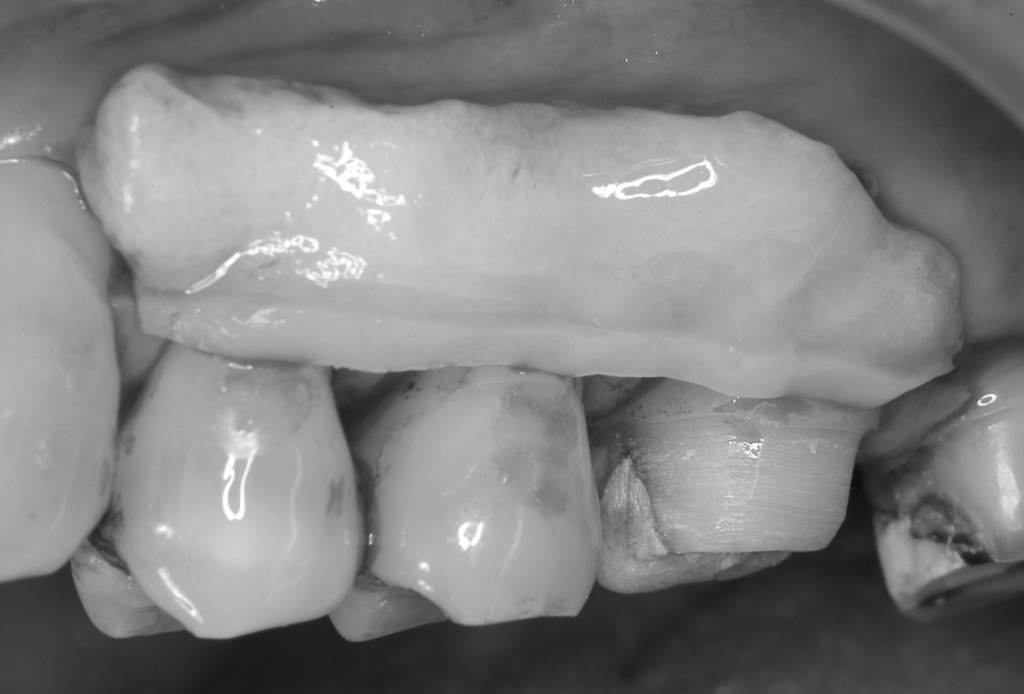

結合組織を採ってきた部分です。採取した後に縫合してあります。ここの傷は術後,硬い食べ物などが当たらないように気をつけていただきます。術後1〜2週間で良くなってきます。

採取した結合組織を,術野に試適しているところです。結合組織が十分なサイズであることがわかります。